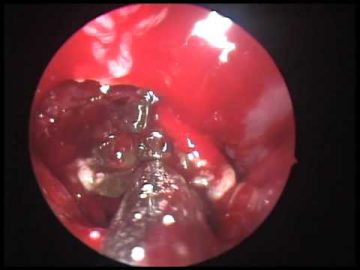

Ход операции

Эндоскопическая гайморотомия обычно выполняется при местном обезболивании, но в некоторых случаях может потребоваться общий наркоз. Перед проведением операции производится тщательное промывание носовой полости и синусов специальными антисептическими растворами. Удаление грибкового тела осуществляется с помощью эндоскопических щипцов. После удаления патологического очага гайморова пазуха повторно обрабатывается антисептическими растворами. Ход операции контролируется с помощью микрокамеры. Средняя продолжительность хирургического вмешательства составляет 20–30 минут.

Обычно, после проведения эндоскопической гайморотомии, отечность в области лица может сохраняться в течение 5–7 дней. В начальный период назначаются препараты от боли и антибактериальные средства, чтобы предотвратить инфицирование раны.